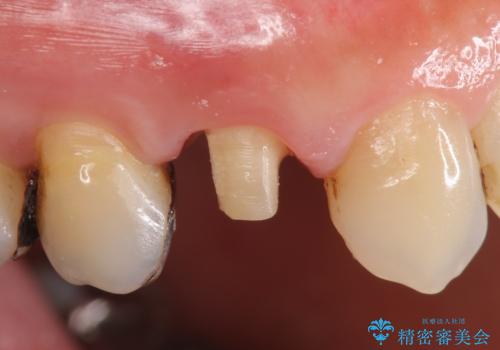

- 右上4番目の歯がなにもしなくてもズキズキ痛むといらっしゃった方の症例です。

検査の結果持続痛も認めたため、虫歯除去後根管治療を行いました。

その後オールセラミッククラウン(エクセレント)による補綴を行いました。